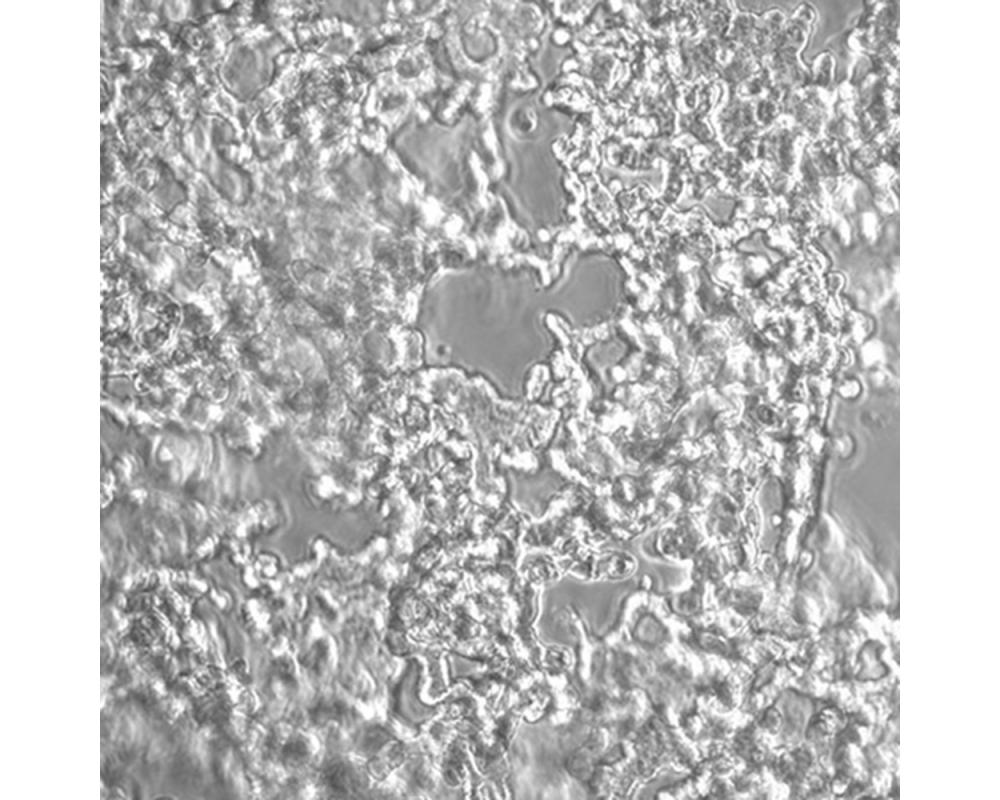

NCI-H526

產品名稱 NCI-H526

中文名稱 人小細胞肺癌細胞

組織來源 小細胞肺癌;骨髓轉移;男性

生長特性 懸浮